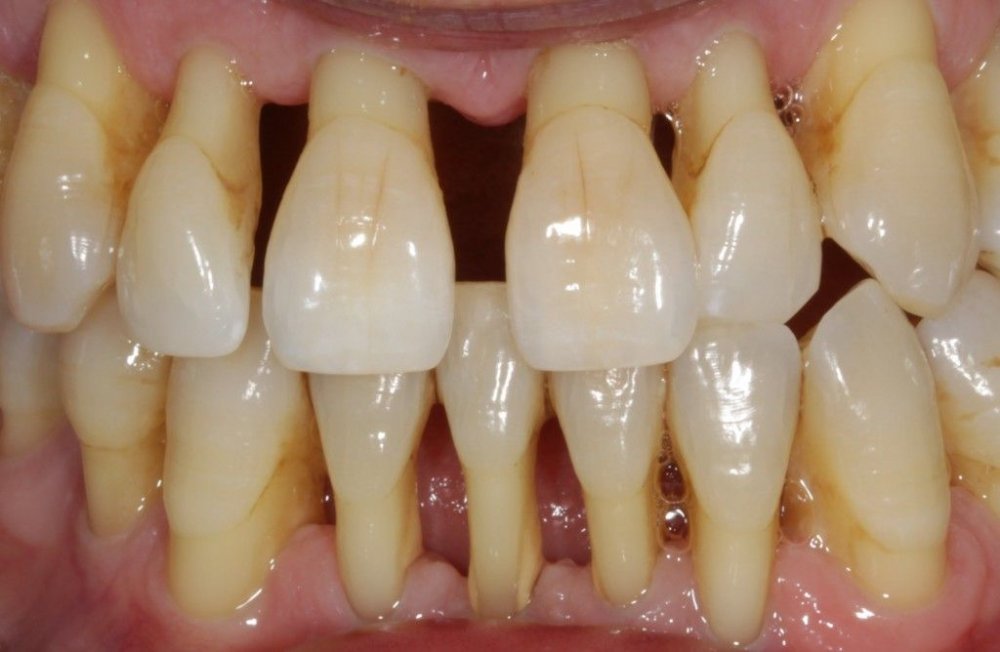

Parodontit tədricən dişətrafı sümük toxumasının itirilməsinə və bakterial plakın daha dərin təbəqələrə keçməsi ilə birlikdə ciddi dərinliklərə çatan sümük defektlərinin (və ya ciblərinin) yaranmasına gətirib çıxarır. Sümük toxumasının itkisi müəyyən bir zaman sonra dişlərdə ciddi hərəkətliliyin yaranmasına və qısa bir müddət sonra itirilməsinə gətirib çıxara bilir.

- Dişlərin laxlaması

- Diş ətlərində çəkilmə